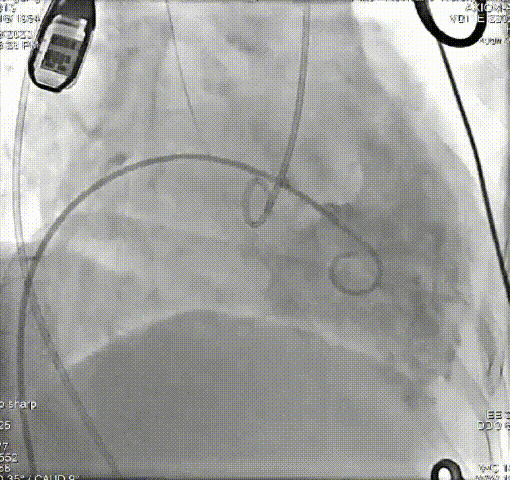

术前、术后造影结果

患者73岁,女性,“心房颤动”病史10年,4年前因“风湿性二尖瓣狭窄、冠心病”于心外科行“二尖瓣生物瓣置换术+三尖瓣成形术+冠脉旁路移植术”。近1年出现活动时气促,1个月来双下肢水肿。心脏超声:重度三尖瓣关闭不全,二尖瓣生物瓣位置及功能未见明显异常。TTVR术后三尖瓣关闭不全消失,无明显瓣周漏。